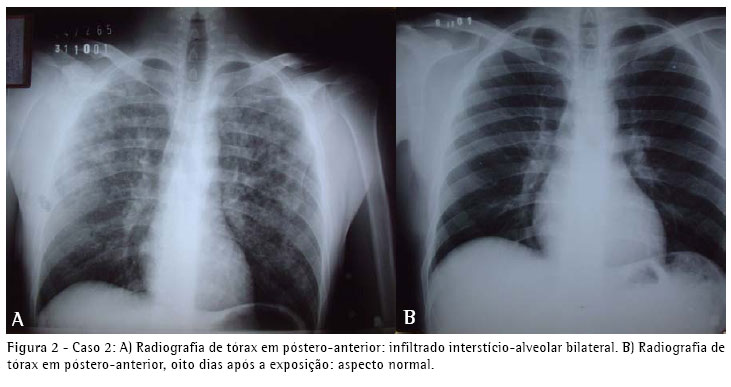

Um segundo paciente era um homem branco, de 33 anos, também residente em Goiânia, subgerente de produção da mesma fábrica de lingüiças. Este paciente informou que realizou a mistura dos produtos citados no caso anterior, sofrendo exposição de aproximadamente 40 minutos. Relatou dispnéia e tosse seca no início da exposição, seguidas por vômitos e dor torácica difusa. Apresentou piora progressiva dos sintomas associada a febre não medida. Relatou que era a primeira vez que manuseava aquela marca de produtos e que os usados anteriormente não liberavam gás quando misturados. Não apresentava antecedentes dignos de nota, exceto tabagismo havia aproximadamente dez anos (dois a três cigarros por dia). Na admissão estava em bom estado geral, eupnéico, afebril, com murmúrio vesicular fisiológico com estertores finos em bases e terço médio dos campos pulmonares. A saturação periférica de oxigênio era de 96% em ar ambiente. Os demais órgãos e sistemas apresentavam-se sem alterações. A radiografia simples do tórax na admissão mostrava infiltrado interstício-alveolar difuso (Figura 2). Ele recebeu alta do setor de emergência com prescrição de prednisona a 40 mg/dia por cinco dias, e depois a 20 mg/dia até o décimo dia, associada a amoxicilina a 1.500 mg/dia por dez dias.

Apresentou melhora progressiva, estando assintomático já no terceiro dia da medicação. Retornou para acompanhamento ambulatorial no oitavo dia após a exposição, quando realizou radiografia de tórax, espirometria, gasometria arterial e teste de difusão do monóxido de carbono, que apresentaram resultados normais.

O quadro clínico e radiológico dos três pacientes foi compatível com edema pulmonar e insuficiência respiratória aguda. A evolução revelou-se favorável e no seguimento clínico, radiológico (Figuras 1, 2 e 3) e de função pulmonar por dezoito meses não apresentaram nenhuma repercussão respiratória.